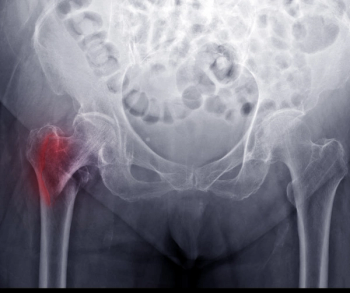

Deep radiomics models that included deep learning features had a 40 percent or greater increase in the specificity rate for diagnosing osteoporosis on hip radiographs in comparison to models that only emphasized clinical and/or textural features.